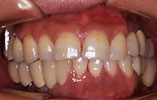

上の前歯1本だけ失った場合 審美的回復

インプラント埋入前

インプラント埋入後

インプラントに

セラミッククラウンを装着

上の前歯1本だけ失った場合、通常両隣りの歯を削ってブリッジを入れますが、インプラント治療によって、健康な歯を削ることなく、審美的にも回復しました。。